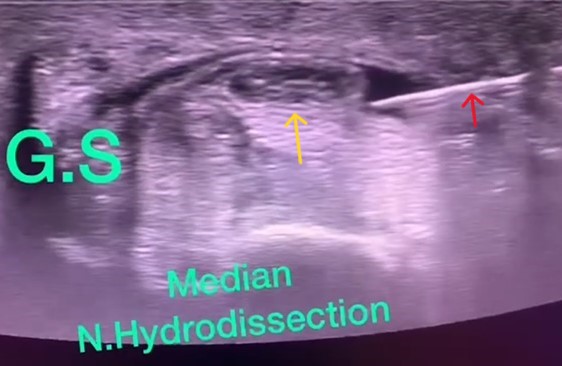

手根管症候群

手の1~4指のしびれを来す疾患で超音波ガイド下に手首手根管内の正中神経周囲に針を正確に刺入し薬剤を注入します